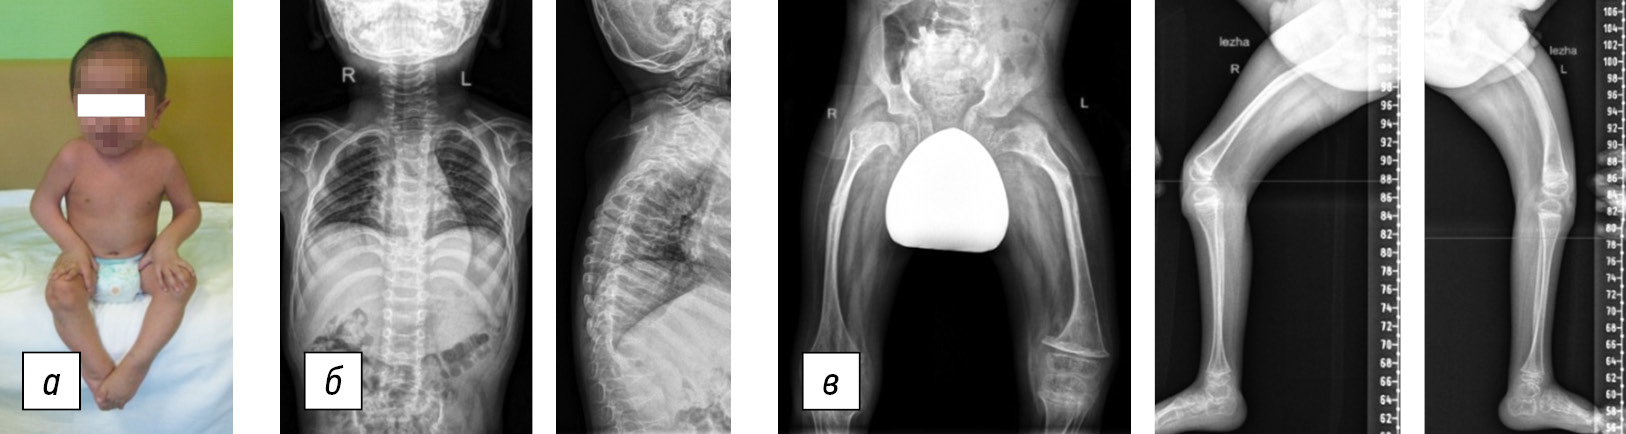

Currently, patient H is a 13-year-old girl with a hypersthenic body build and a height of 125 cm. She uses crutches to walk indoors. Her head is positioned along the midline, and her neck is short. Mandibular asymmetry with displacement to the right is noted. The spinal axis is curved in both the frontal and sagittal planes, resulting in kyphoscoliosis in the thoracolumbar region and hyperlordosis in the lumbar region. No limitations are observed in the movements of the shoulder, elbow, and wrist joints, and the hands are in a neutral position. Additionally, a valgus deformity is present in the right lower extremity. There is flexion in the hip joints up to 90°, with minimal rotational movements that are moderately painful. There is a 20° extension deficit in the knee joints, and flexion is possible up to 80° on both sides. The feet are in a neutral position.

The anteroposterior and lateral projections of the panoramic radiograph of the spine revealed a kyphotic deformity of 33° (ThIX–LII) and a scoliotic deformity of 40° (ThIX–LXII), with the sacrum horizontal and coccyx at a 90° angle (Fig. 2). Magnetic resonance imaging of the craniovertebral region indicated an Arnold-Chiari anomaly of the first degree. Table 1 presents the densitometry parameters’ dynamics between the ages of 6 and 13 years. After a long period of gradual increase, a repeated decrease in skeletal bone mineral density due to a long treatment break (9.5–11 years) was observed. Blood analysis showed high C-terminal telopeptide (2.63 ng/mL; normal range: 1.63–1.94 ng/mL) at the beginning of treatment. Currently, the level has normalized (1.68 ng/mL). Throughout the observation period, persistent and pronounced vitamin D deficiency (last value: 7.3 ng/mL; normal range: 30–80 ng/mL) was detected. The additional parameters of bone tissue metabolism, including calcium, phosphorus, alkaline phosphatase, osteocalcin, N-terminal propeptide, and parathormone, were within normal limits.

Fig. 2. Patient H, 13 years old, Bruck syndrome, type 2: a, general view of the patient; b, anteroposterior and lateral radiographs of the spine: 40° right scoliotic deformity, 33° kyphosis, platyspondylia, and sacrococcygeal changes